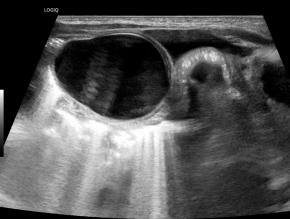

[359,Pediatric [Ped]] 1/F,Abdominal cyst was detected on prenatal ultrasound.

Modality US,

실제 이미지 실제 이미지